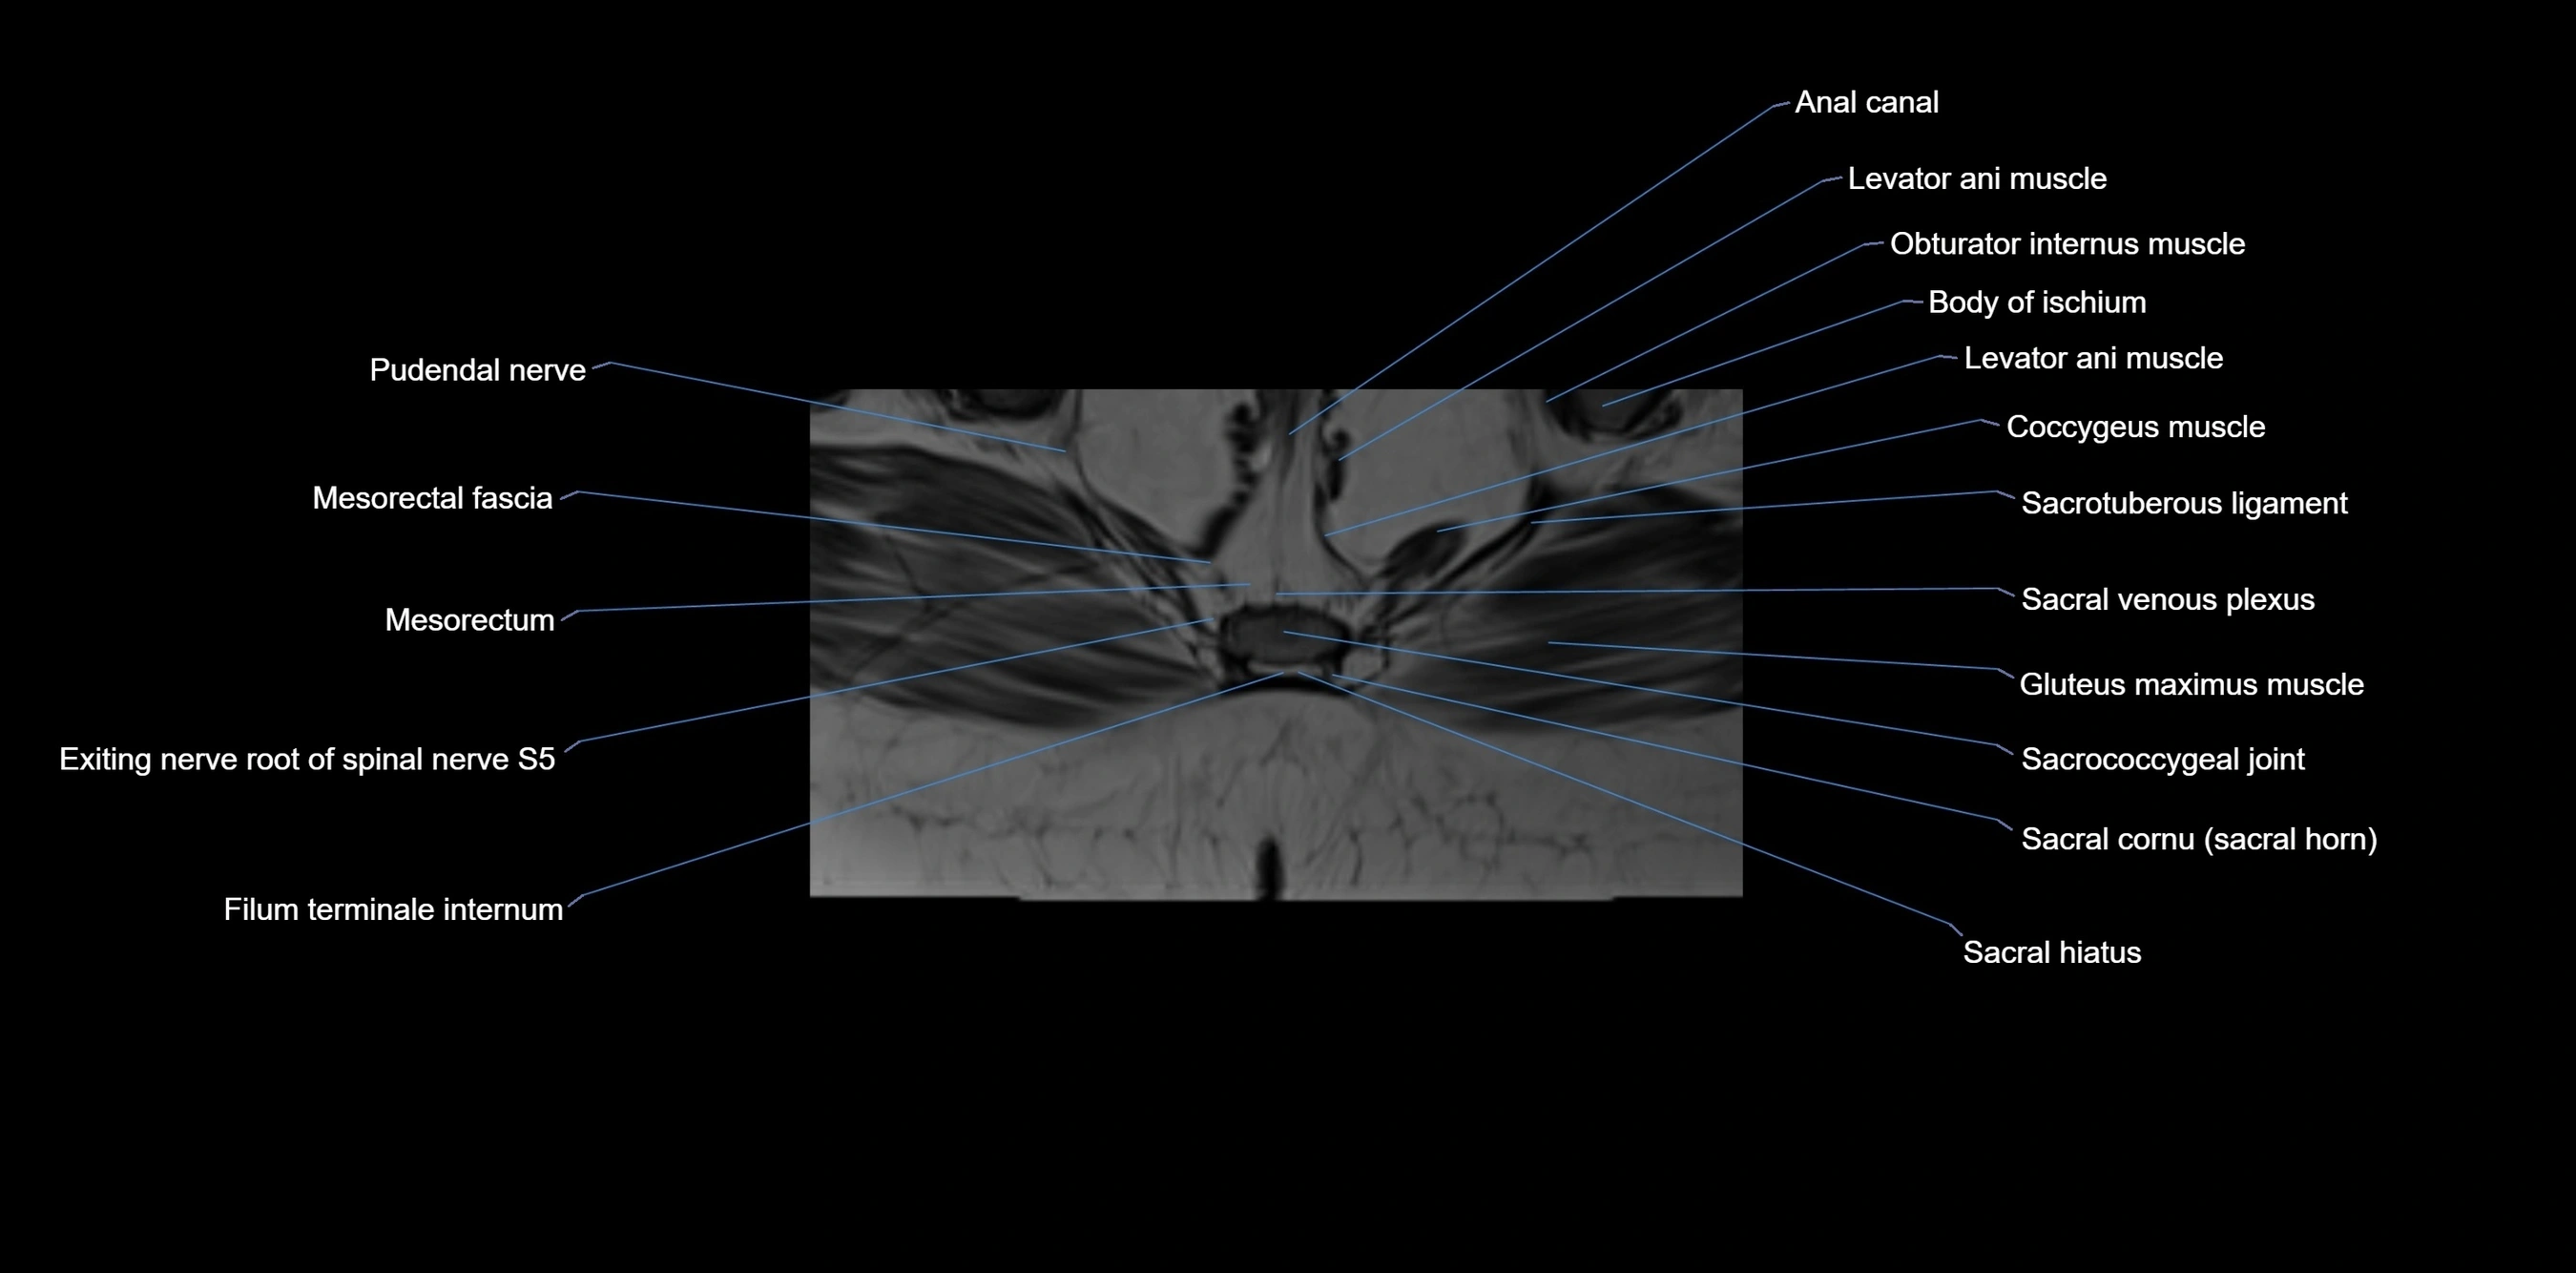

CT image

image